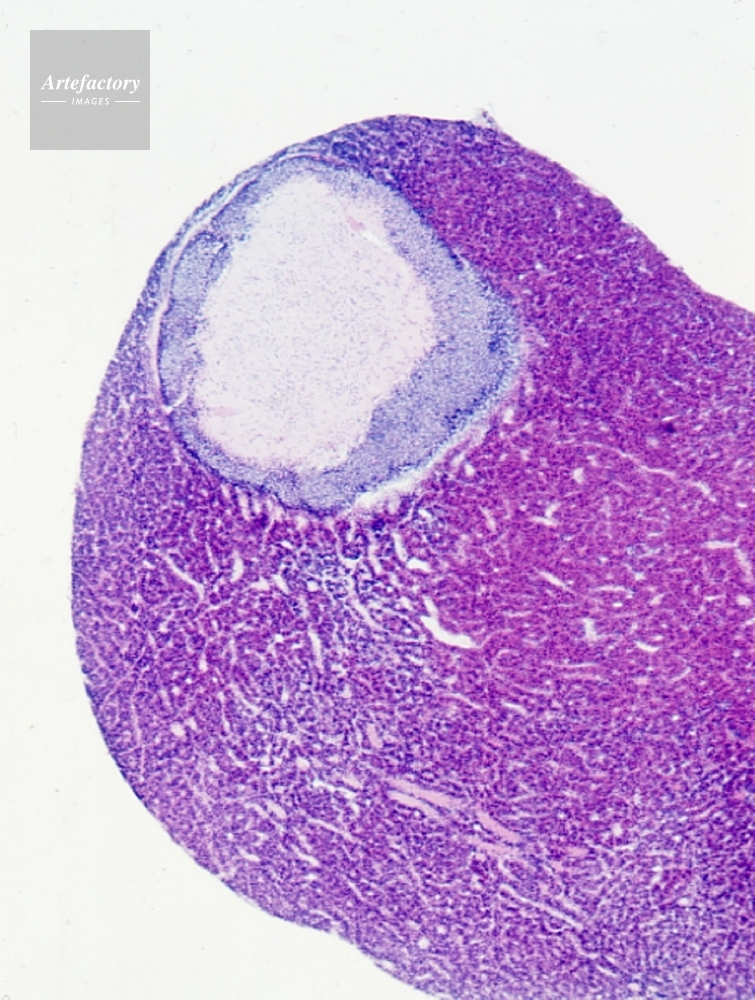

| 作品タイトル | サル脳下垂体 | モデルリリース | なし | |

| キャプション | ヘマトキシリンエオシン染色、長辺55mmの場合 15倍 | 制限事項 | こちらはポジのみの画像です。貸出中につきご提供できない場合はご了承ください。 | |